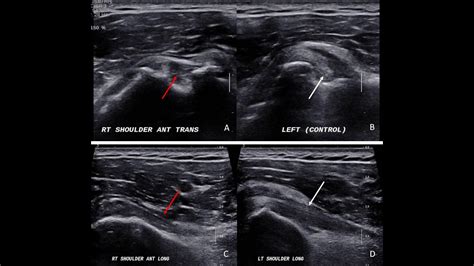

Diagnosing Biceps Femoris Tendinosis

Diagnosing Biceps Femoris Tendinosis involves a combination of physical examination and imaging tests. A healthcare professional will typically:

• Imaging Tests: Order imaging tests such as ultrasound or MRI to visualize the tendon and confirm the diagnosis. These tests can help identify degeneration, thickening, or other abnormalities in the tendon.